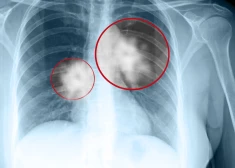

Par veselību24.08.2024Lielbritānijā uzsākta daudzsološa terapija cerībā radīt jaunu ēru plaušu vēža ārstēšanā

Par veselību07.07.2023Plaušu vēža izplatība pirmo reizi vēsturē Lielbritānijā sievietēm lielāka nekā vīriešiem. Ārsti zina, kāpēc

Par veselību07.07.20238 mazāk zināmas plaušu vēža pazīmes, kas jāzina, lai ļauno slimību pamanītu laikus

Par veselību01.02.2023Visizplatītākais vēža izraisītas nāves cēlonis - plaušu vēzis! Ko atklāj Eiropas vēža uzveikšanas plāns?